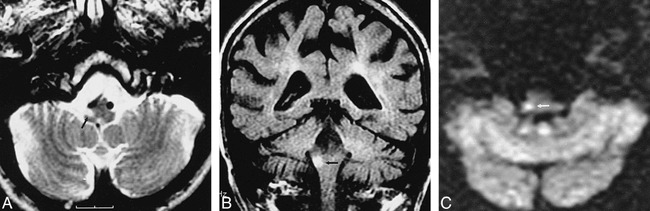

fig 1.

74-year old patient scanned 14 hours after onset of vertigo.

A, FSE T2-weighted image reveals an old left cerebellar lacuna (arrow).

B, FLAIR image shows no cerebellar signal abnormality.

C, Diffusion-weighted image sensitive to water motion in the craniocaudal direction reveals an acute infarct in the right cerebellar hemisphere (arrow).